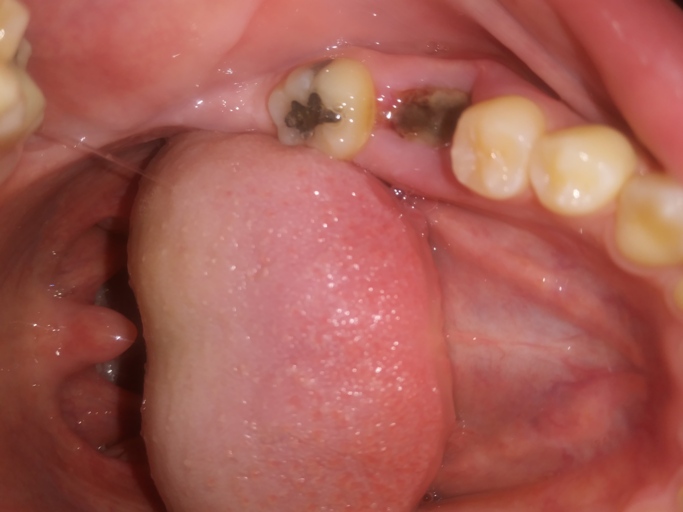

Is this normal healing of extraction sites

I had 2 wisdom and 2 molars removed as of now 5 days ago and these photos were taken on day 3, I was concerned that they may be infected, but there is no pain or outrageous swelling, no bleeding either and I can't really tell if there is a bad smell...